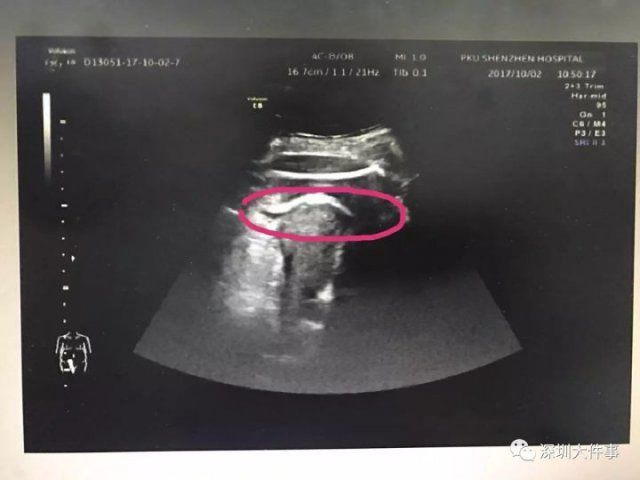

医生初步怀疑患者子宫破裂,当即安排做了 B 超。检查发现,胎儿的一条腿 " 踢破 " 了子宫,进入了腹腔,大腿根正卡在子宫壁上!

▲红色圆圈处是胎儿的腿,已经伸到子宫壁外